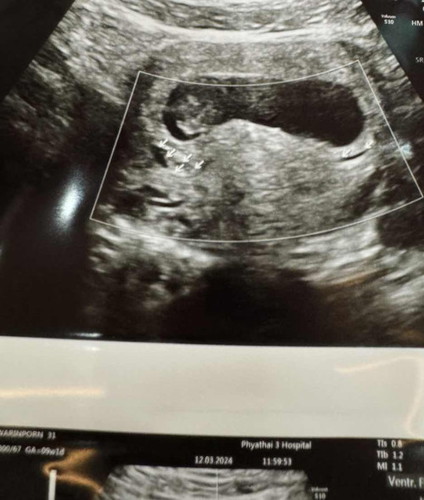

เรามีเลือดออกด้านในรอบถุงตั้งครรภ์ แต่ไม่ออกมาด้านนอก อยากให้แม่ๆช่วยแชร์ดูแลตัวเอง และอาหารที่ทานในภาวะแท้งคุกคามหน่อยค่ะ